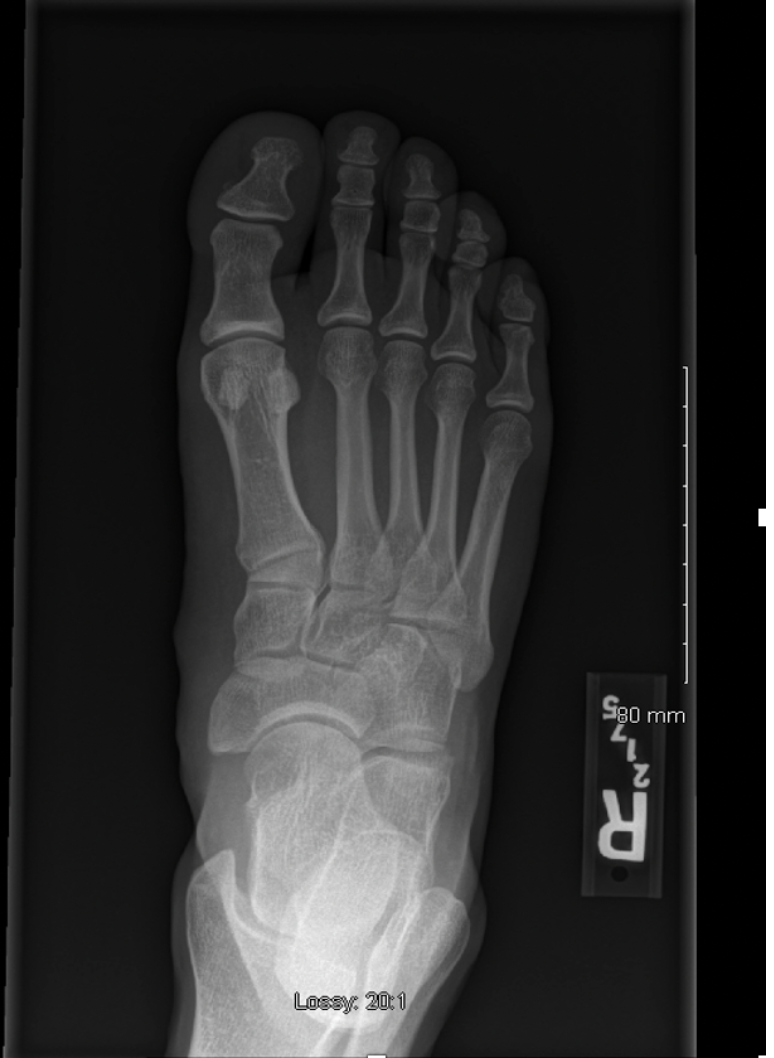

Q

What view is this?

A

DP